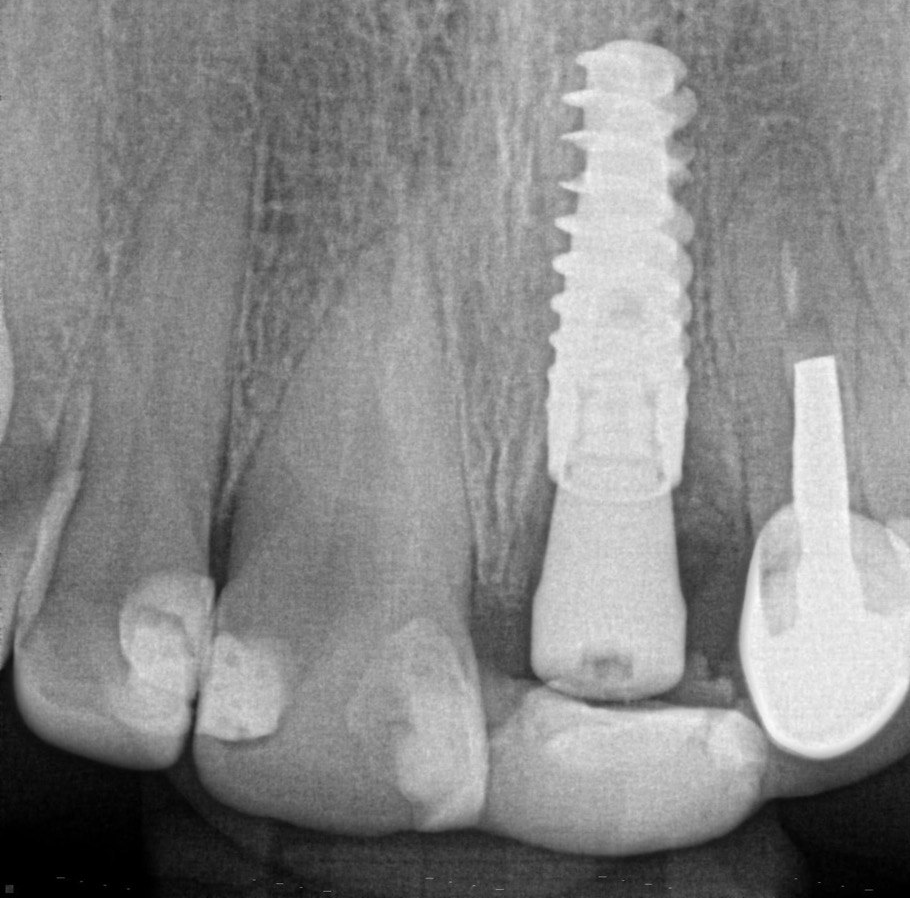

1. What option can be selected regarding the implant seen in this X ray?